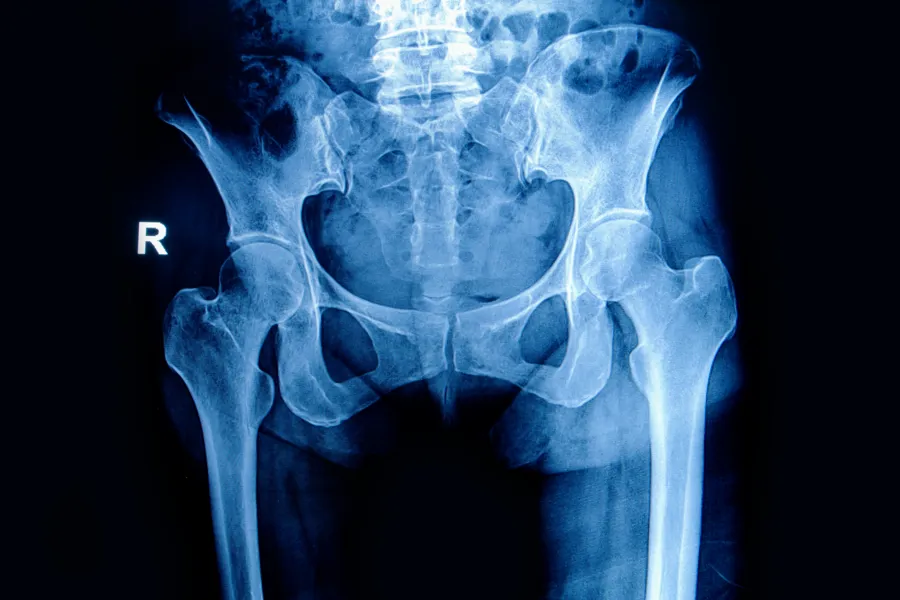

Foto: Cato Kjærvik